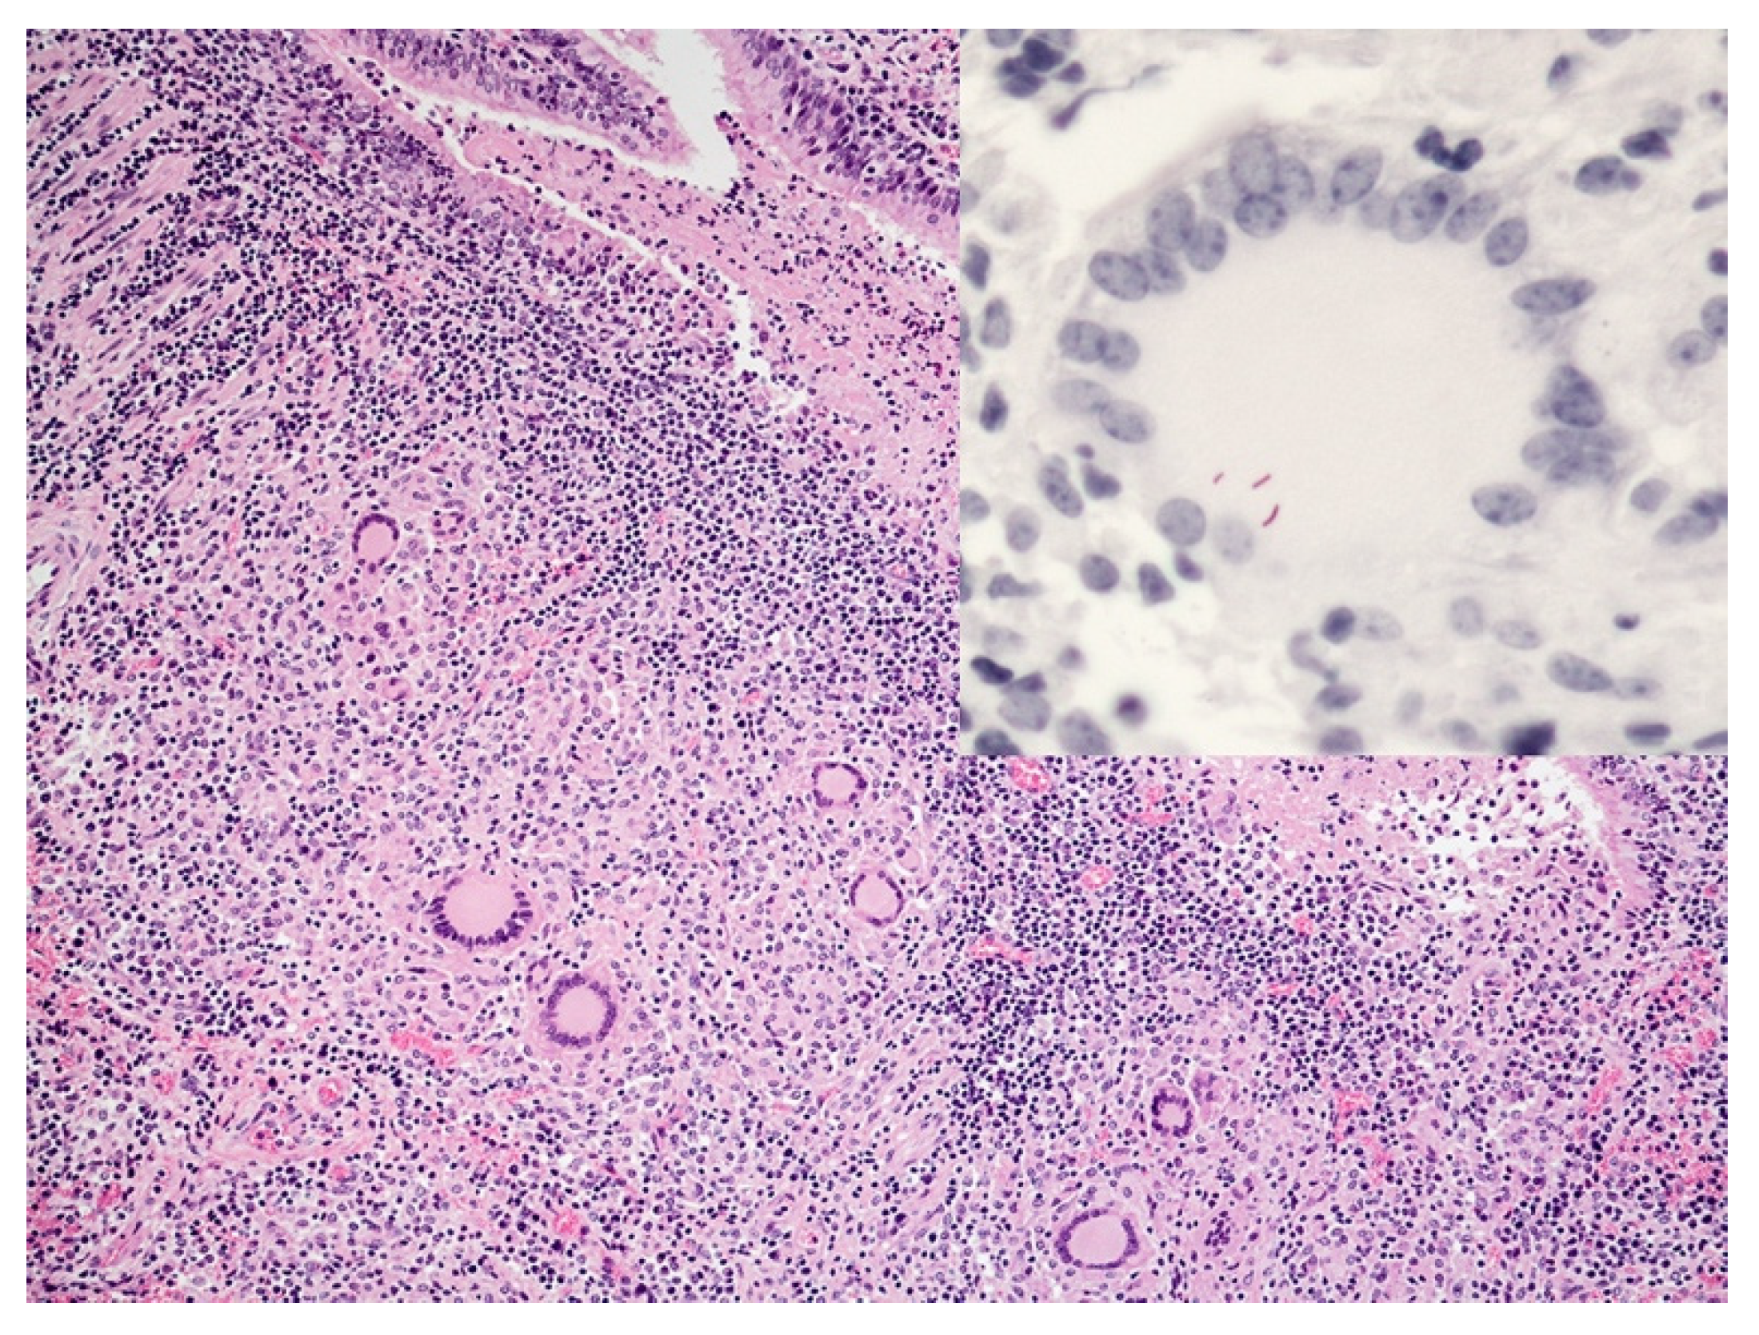

- Palmer, M.V.; Wiarda, J.; Kanipe, C.; Thacker, T.C. Early pulmonary lesions in cattle infected via aerosolized Mycobacterium bovis. Vet. Pathol. 2019, 56, 544–554. [Google Scholar] [CrossRef]

- Cassidy, J.P.; Bryson, D.G.; Pollock, J.M.; Evans, R.T.; Forster, F.; Neill, S.D. Early lesion formation in cattle experimentally infected with Mycobacterium bovis. J. Comp. Pathol. 1998, 119, 27–44. [Google Scholar] [CrossRef]

- Aranday-Cortes, E.; Bull, N.C.; Villarreal-Ramos, B.; Gough, J.; Hicks, D.; Ortiz-Pelaez, A.; Vordermeier, H.M.; Salguero, F.J. Upregulation of IL-17A, CXCL9 and CXCL10 in early-stage granulomas induced by Mycobacterium bovis in cattle. Transbound. Emerg. Dis. 2013, 60, 525–537. [Google Scholar] [CrossRef]

- Cassidy, J.P.; Bryson, D.G.; Gutierrez Cancela, M.M.; Forster, F.; Pollock, J.M.; Neill, S.D. Lymphocyte subtypes in experimentally induced early-stage bovine tuberculous lesions. J. Comp. Pathol. 2001, 124, 46–51. [Google Scholar] [CrossRef]